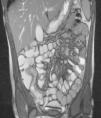

Técnica de resonancia magnética intestinalSe realizó el estudio mediante 1,5 tesla MR (Avanto, Siemens). Se colocó al paciente en decúbito prono para disminuir la motilidad intestinal12. Se estableció un protocolo con las siguientes secuencias: 3 planos T2 HASTE con o sin Fat SAT, axial y coronal T2 true-FISP, axial y coronal T1 Fat-SAT VIBE pre y poscontraste por vía intravenosa (gadolinio), HASTE dinámico y axial difusión: DWI epi2diff b0/b1000. Las RMI fueron valoradas por un mismo radiólogo, evaluando las siguientes variables: la calidad de la prueba (según la distensión abdominal y la progresión del contraste intestinal); el engrosamiento de pared intestinal mediante (T2 HASTE, true-FISP T2) (figs. 1 y 2), la hipercaptación mucosa (T1 pre y posgadolinio), las complicaciones extraintestinales (fístulas, abscesos, flemones, adenopatías (> 5mm), hiperemia mesentérica, líquido libre, estenosis, trastornos de motilidad) y la extensión de intestino afectado. En función de estos parámetros, clasificamos a los pacientes en 5 patrones (tabla 1).

Valoración de actividadConsiderando la zona con máxima afectación y analizando los parámetros de engrosamiento de la pared intestinal y de hipercaptación mucosa según los patrones de RMI anteriormente descritos, encontramos: 5 estudios con patrón de normalidad, 3 con patrón fibrosis, 4 con afectación leve, 4 con afectación moderada y 6 con afectación severa13. Encontramos una relación estadísticamente significativa entre los patrones de RMI y PCR (p=0,047), VSG (p=0,006) y PCDAI (p=0,002). Los pacientes en remisión (grupo 0) o con un patrón de fibrosis (grupo 1) presentaban menor score PCDAI y menores cifras de VSG y PCR, siendo estos parámetros mayores en los grupos 2, 3 y 4 (tabla 2). Los pacientes clasificados en los patrones 2, 3 y 4 de RMI mostraron elevación de PCDAI y parámetros inflamatorios superiores a los de los grupos 0 y 1, siendo estos resultados significativamente superiores entre el grupo 0 y el grupo 4 (p=0,004). El resto de las comparaciones entre grupos no fueron significativas debido al tamaño muestral. Analizamos por separado cada uno de los elementos que componen el score de RMI: el engrosamiento de la pared intestinal y la hipercaptación de mucosa; ambos parámetros se relacionan con la actividad de la enfermedad (PCDAI), siendo solo significativa (p<0,001) para esta última; la presencia en nuestra serie de 3 pacientes con patrón fibrosis explica estos resultados.

La actividad de la enfermedad fue valorada según el engrosamiento de la pared intestinal y la captación mucosa, estableciendo una relación significativa entre nuestros patrones y PCR (p=0,047), VSG (p=0,006) y PCDAI (p=0,002). La RMI nos permitió diferenciar lesiones con actividad inflamatoria y lesiones fibrosas o pacientes en remisión12,23. Nuestro escaso tamaño muestral no permitió establecer diferencias significativas entre la gradación de RMI y los hallazgos anatomopatológicos aunque están descritos por otros autores13,24.